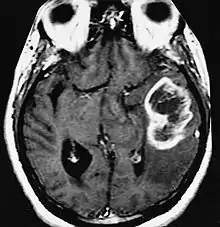

| An example of a ring-enhancement around a lesion in gliobastoma. In tumefactive multiple sclerosis, the ring-enhancement is open, not forming a complete ring. |

These atypical lesion characteristics include a large intracranial lesion of size greater than 2.0 cm with a mass effect, edema and an open ring enhancement. A mass effect is the effect of a mass on its surroundings, for example, exerting pressure on the surrounding brain matter. Edema is the build-up of fluid within the brain tissue. Usually, the ring enhancement is directed toward the cortical surface.[2] The tumefactive lesion may mimic a malignant glioma or cerebral abscess causing complications during the diagnosis of tumefactive MS. T2-hypointense rim and incomplete ring enhancement of the lesions on post-gadolinium T1- weighted imaging on brain MRI enable accurate diagnosis of TDL[3]

Diagnosis of tumefactive MS is commonly carried out using magnetic resonance imaging (MRI) and proton MR spectroscopy (H-MRS). Diagnosis is difficult as tumefactive MS may mimic the clinical and MRI characteristics of a glioma or a cerebral abscess. However, as compared to tumors and abscesses, tumefactive lesions have an open-ring enhancement as opposed to a complete ring enhancement.[1] Even with this information, multiple imaging technologies have to be used together with biochemical tests for accurate diagnosis of tumefactive MS.[36]

MRI diagnosis is based on lesions that are disseminated in time and space, meaning that there are multiple episodes and consisting of more than one area.[39] There are two kinds of MRI used in the diagnosis of tumefactive MS, T1-weighted imaging and T2-weighted imaging. Using T1-weighted imaging, the lesions are displayed with low signal intensity, meaning that the lesions appear darker than the rest of the brain. Using T2-weighted imaging, the lesions appear with high signal intensity, meaning that the lesions appear white and brighter than the rest of the brain. When T1-weighted imaging is contrast-enhanced through the addition of gadolinium, the open ring enhancement can be viewed as a white ring around the lesion.[40] A more specific MRI, Fluid attenuation inversion recovery (FLAIR) MRI show the signal intensity of the brain. Subjects with tumefactive multiple sclerosis may see a reduction of diffusion of the white matter in the affected area of the brain.[11]